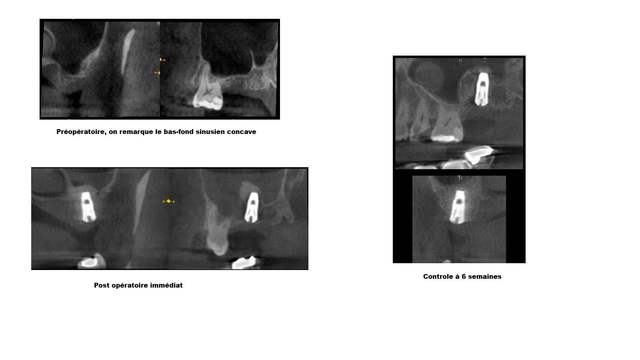

jeune femme de 32 ans sans antécédent médicaux particulier consulte pour le remplacement de la 26 par un implant.

Extraction de la dent par un confrère au mois d'octobre dernier suite à une infection ( d’après les dires de la patientes).

Je mets en pièce jointe le scan.

C'est la première fois que je vois une forme de sinus comme celle la, et j'ai peur qu'avec un sinus lift le decollement de la membrane soit plutôt galère, et le summers ne me rassure pas non plus.

effectivement, quand on vois la coupe 86, pas evident de décoller sans déchirer.

Ceci étant, dans un cas comme celui là , il peut être bon d'attendre un peu car les suites de l'extraction ne semblent pas optimum, mais une voie crestale me parait suffisante, car si déchirure de la membrane,ceci ne va pas mettre en cause la survie de l'implant.

Par contre implant stable à la pose??? vu les coupes ça va dépendre de la position.

+1 coupe 86 87 c'est vraiment pas beau ...

on dirait qu'il y a une solution de continuité au niveau de la gouttière de l'artère palatine.

je pense aussi que le crestal suffit

voilà un cas similaire traité en crestal assisté d'un insert pour soulever avec la force hydraulique la membrane